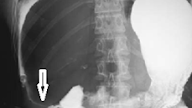

This is radiology images of Oriental cholangiohepatitis. Computed tomography reveals stones (arrows) within dilated intrahepatic bile ducts.

In some patients the sphincter of Oddi is destroyed, with reflux of gas and intestinal content into bile ducts. At times orally ingested contrast refluxes into the bile ducts. Stones and air bubbles can be confused with each other. Computed tomography can suggest the diagnosis by detecting dilated intrahepatic bile ducts and stones. Once the diagnosis is suspected, ERC defines the underlying anatomy using, if necessary, a balloon catheter to dilate and obtain adequate filling of intrahepatic ducts. At times percutaneous cholangiography is necessary to outline the full extent of hepatolithiasis.